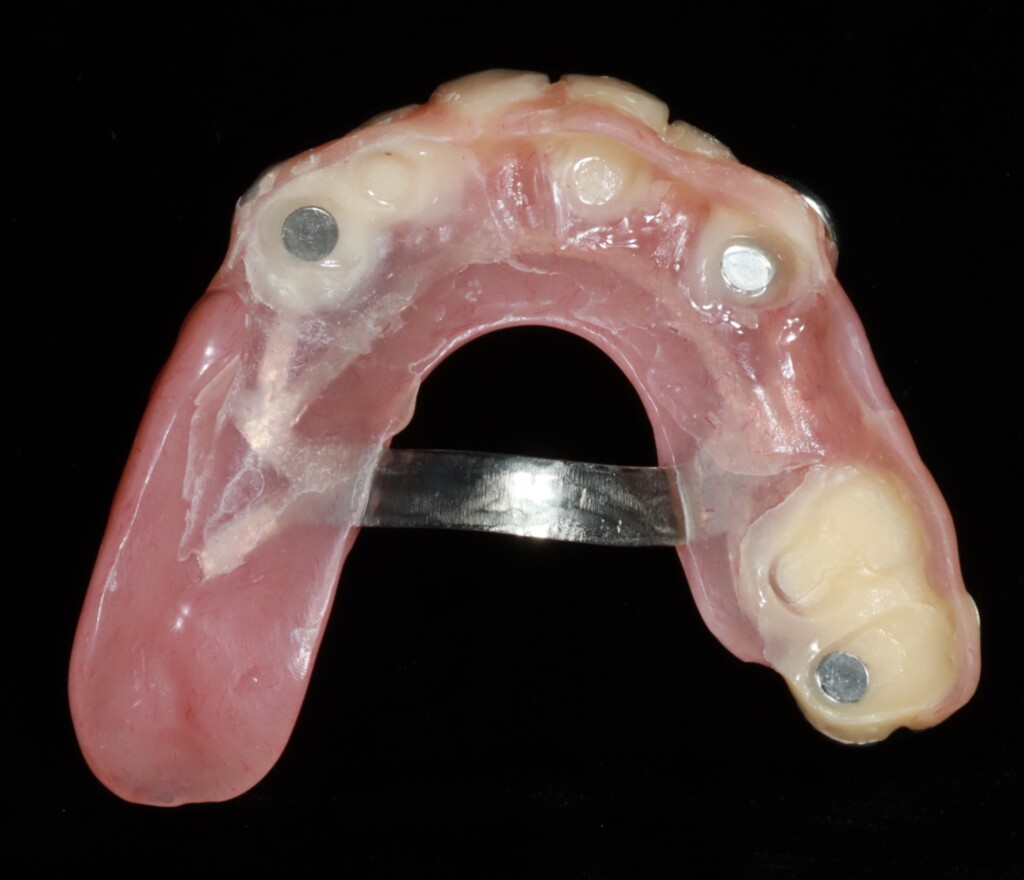

磁性アタッチメントが装着された状態(上顎)

仮歯と仮入れ歯を修理して作った磁石で安定する仮入れ歯

磁性アタッチメントは、歯に引っかけて入れ歯を固定するのではなく、磁石の力でくっつけることで入れ歯を安定させる仕組みです。そのため、硬いものを噛むなど、食事中に横から無理な力がかかった場合でも、歯に負担がかかり続けるのではなく、自然に外れることで力を逃がす構造になっています。一方で、強く固定する構造ではないため、安定感には一定の限界があります。過度な力がかかった際には外れて歯を守る仕組みであるため、状況によっては外れやすいと感じることがあります。また、磁性アタッチメントは、歯の側に装着する「磁性金属(キーパー)」と、義歯の内側に組み込まれる「磁石構造体(マグネット)」で構成されています。磁性金属とは、普段は磁石ではありませんが、磁石が近づくと引き寄せられる性質をもつ金属です。義歯に内蔵される磁石は医療用として安全性が確認されており、お口の中で長期間使用することを前提に設計されています。そのため、通常の使用で体に影響が出ることはほとんどありません。ただし、MRI検査の際には、磁石の影響により、あごや顔まわり(口元付近)の画像が見えにくくなる可能性があります。そのため、事前に医師や検査スタッフへ申告が必要です。検査部位によっては画像に影響が出る場合があるため、状況に応じて義歯の取り外しを検討することがあります。